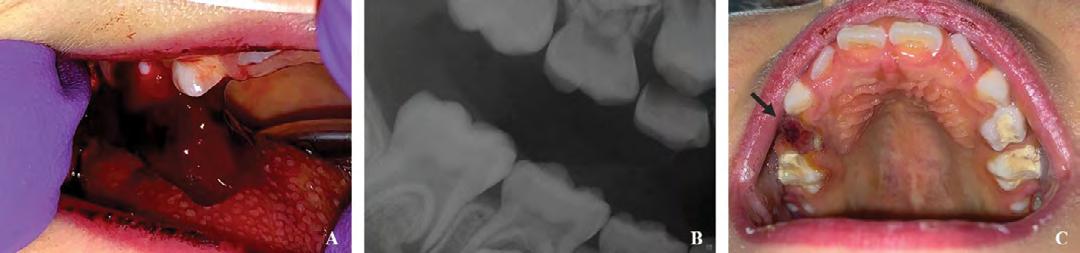

A large liver-like clot was removed in order to perform a clinical examination and ice water-soaked gauze was placed on the site with gentle pressure without improvement. Extraoral evaluation was not significant. Removal of the gauze revealed continuous oozing of heme localized to the gingival sulcus of the mandibular right permanent first molar (Figure 1A), which had a PMC placed one day prior. The radiograph (Figure 1B) revealed normal dental development for chronological age, multiple restorations on the permanent and primary dentition, and no radiographic radiolucency indicating signs of pathology. Proximity was noted on the distal margin of the PMC on the mandibular right permanent first molar to the adjacent tooth follicle.

Local anesthetic infiltration in the form of 2% lidocaine with 1:100,000 epinephrine was administered surrounding the affected area, and the gingival sulcus was curetted and irrigated with saline solution to remove any local irritants. The gingival sulcus was packed with a gelatin matrix and the gingival tissues cauterized. Hemostasis was achieved, and the patient was instructed to provide continuous biting pressure (Figure 1C). The patient was discharged and received follow-up care in the outpatient dental clinic the next day, at which time she was exhibiting absence of bleeding complications and normal healing gingival tissues.

lary left permanent first molar region (Figure 2A). Figure 1: (A) Bleeding localized to lower right quadrant, from distal segment (black arrow) of gingival sulcus of lower right permanent first molar, post-removal of currant jelly-like clot. (B) Imaging revealed intact restorations and no radiolucencies or pathology. Close proximity of distal margin of preformed metal crown on lower right permanent first molar to dental follicle of lower right permanent second molar was noted (white arrow). (C) Area surrounding lower right permanent first molar with hemostasis achieved using local hemostatic measures.

Figure 2: (A) Currant jelly-like clot by extraction site in upper right quadrant. (B) Removal of currant jelly-like clot. (C) Extraction site with hemostasis achieved using socket curettage and local hemostatic measures.